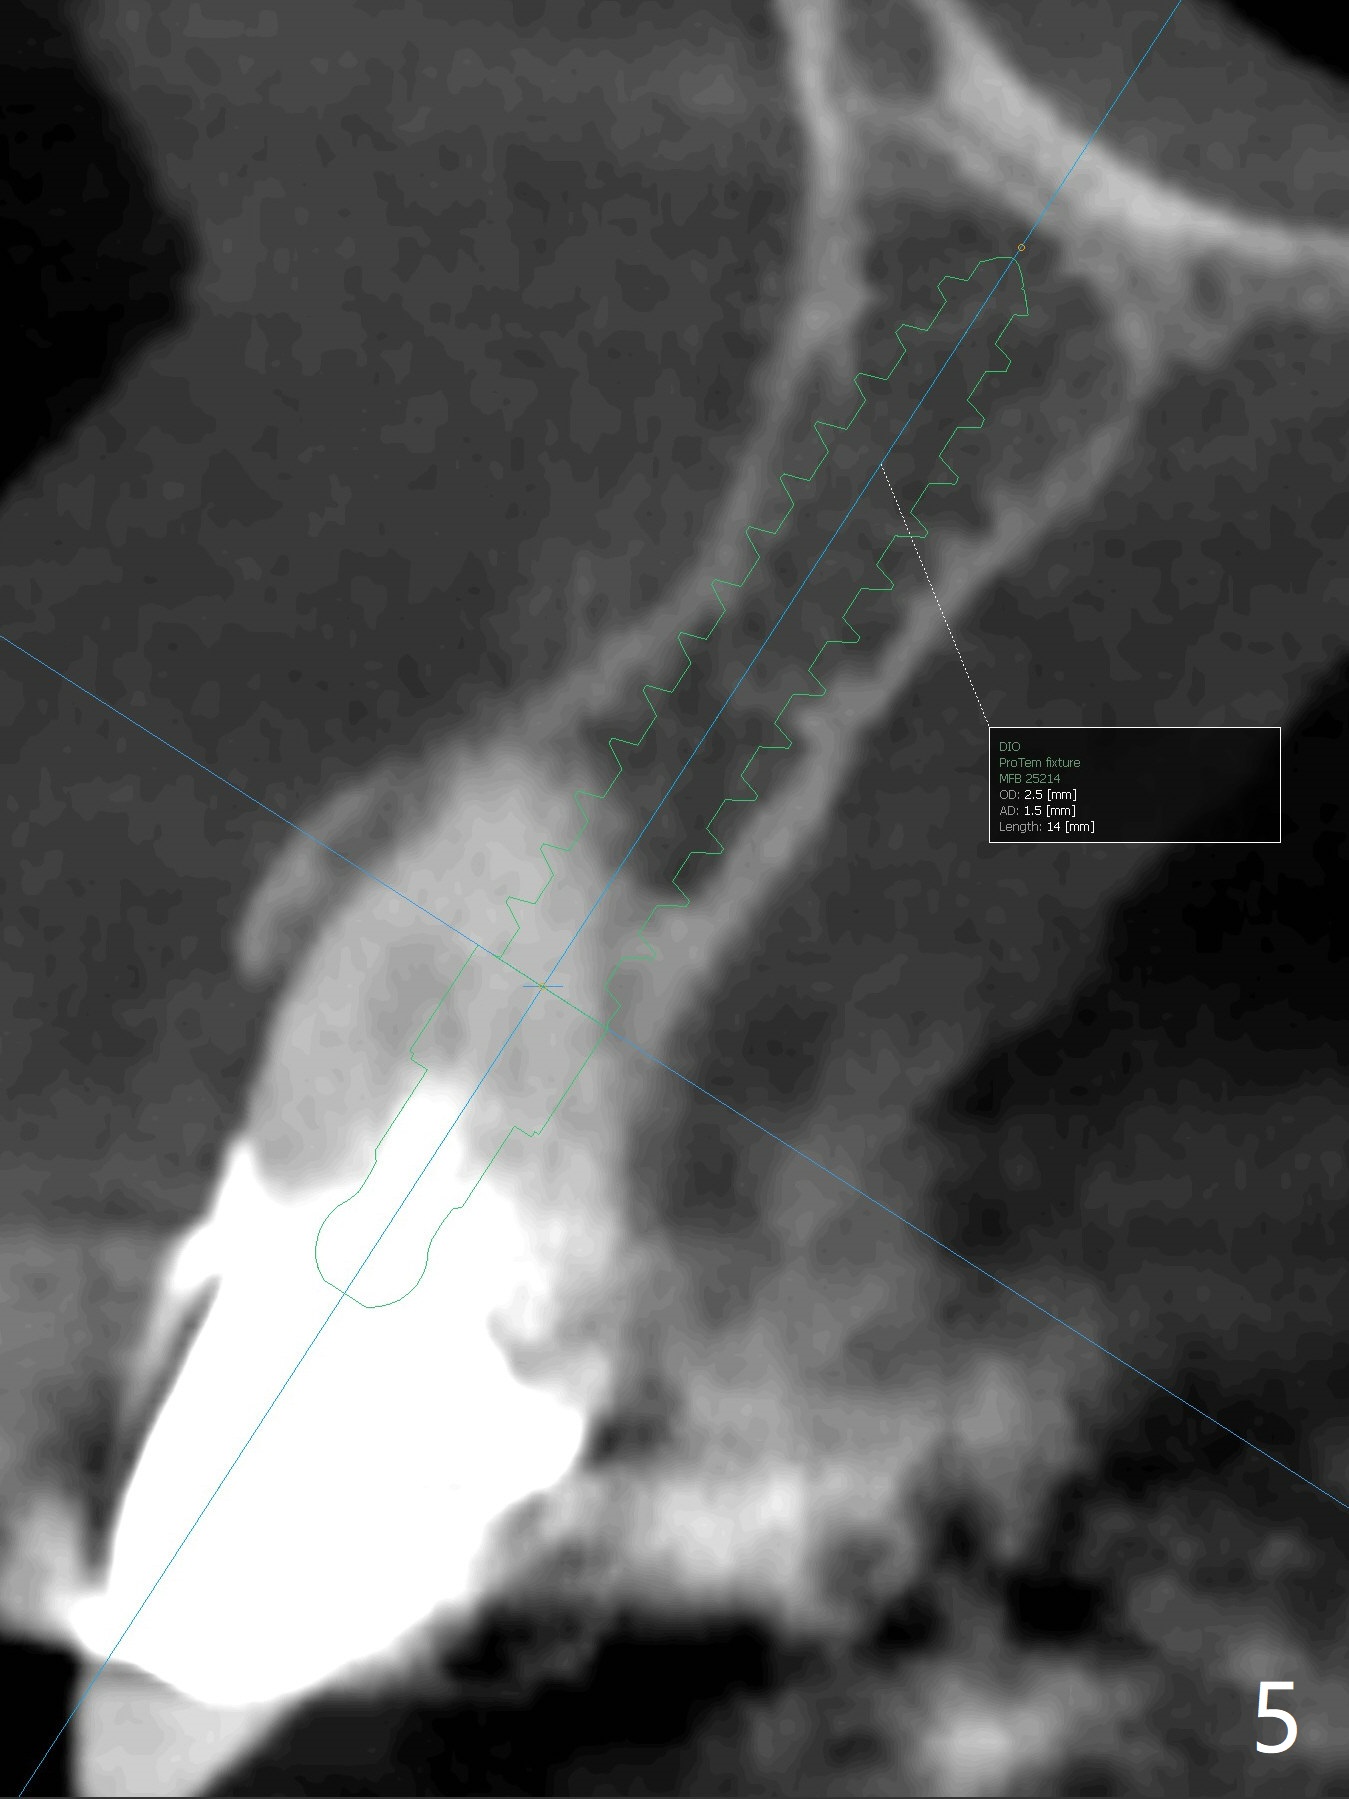

A 67-year-old woman has multiple restoration (difficult for guide preparation). The tooth #6 fractures equigingival with a separated file (Fig.1 <). Because of missing #7, the gingival embrasure between #6 and 8 is large (*). To reduce it, the mesial crest will be trimmed by using 6 mm profile drill after placement of a 3.5x13 mm FC implant (low bone density) and a narrow temporary abutment is going to be used to squeeze the papilla coronally and mesially. In a coronal section, osteotomy will be initiated in the middle of the palatal slope of the socket (Fig.2). A 4 mm x15 degree ~3 mm cuff angled abutment may be used before impression. Take preop photos to show the large gingival embrasure between #6 and 8. The other way to reduce the gingival embrasure is to place an implant mesially. It appears that a 3.5 mm implant is too large for the mesial ridge (Fig.3), while a 2.5 mm one is proper (Fig.4,5).